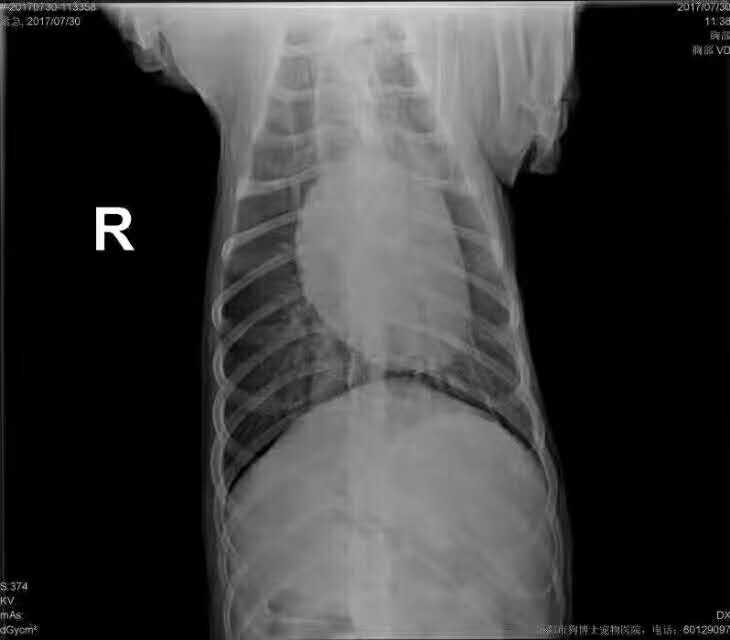

薩摩耶腫瘤摘除:     酸奶,薩摩耶,***長期***不止,B超卵巢有數(shù)個卵巢囊腫,確診為乳腺腫瘤?犬傳染性性病腫瘤(TVT),遂施絕育?乳腺增生?TVT摘除術(shù),順利完成,期待*。